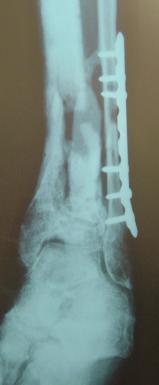

Pre-corrective surgery X-Rays of the damaged right & left legs / ankles

These x-rays were taken at Dr Armendariz’s office, just prior to performing any corrective surgery. As can be seen in these images,

there was no tibia bracing provided by Dr. Keller. Liam was released from Dr Keller’s care with instructions that full weight bearing could

be accomplished within 2 months of Keller’s last surgical procedure. The best example to examine is the second image (from the left) of the

top how. Notice how the bones that should be aligned with the tibia are in fact on the other side of the leg. The third image shows how badly

Liam’s left foot was twisted as a result of the pool placement of the external fixation. What is not obvious is that the screw at the bottom

of the plate on the right fibula missed being screwed into the plate.